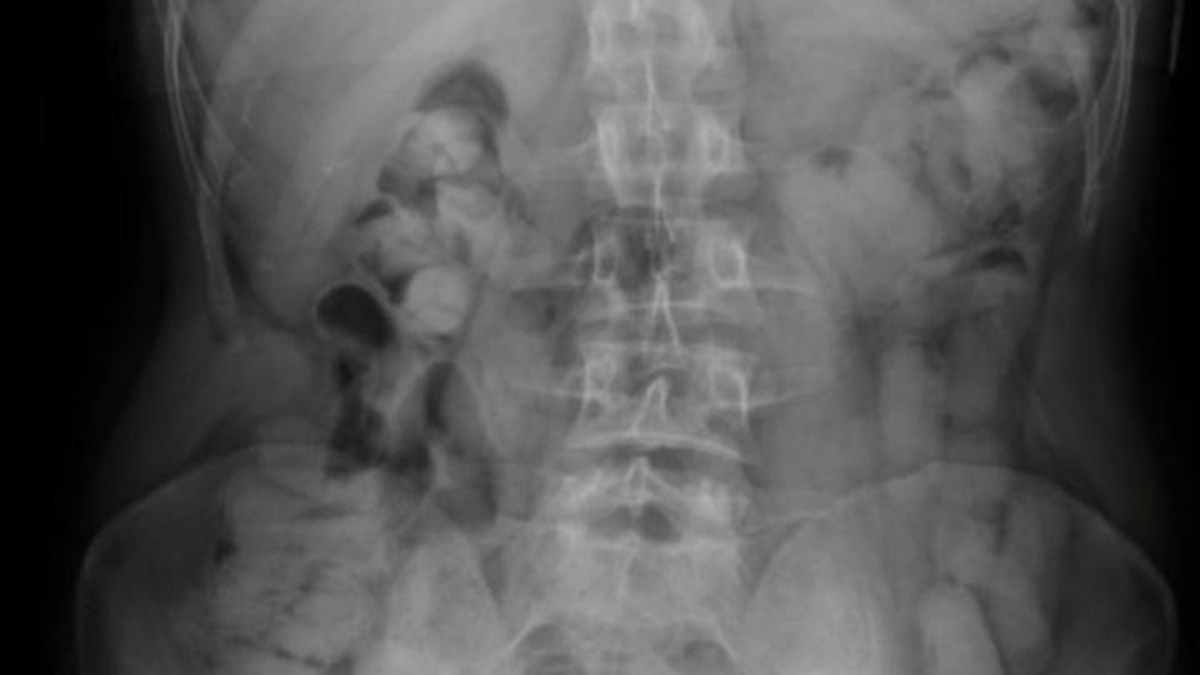

Ante la presunción de estar frente a un hecho ilícito, los uniformados tomaron contacto con el Juzgado Federal de Tucumán, el cual autorizó el traslado de los ciudadanos hacia el nosocomio local, a los fines de efectuar las placas radiográficas.

Tres ciudadanos bolivianos quedaron detenidos por ingerir 235 cápsulas con cocaína. Foto: Argentina.gob.ar

Los resultados de los estudios médicos confirmaron la presencia de cuerpos extraños en el interior de los estómagos de los pasajeros, quienes inmediatamente quedaron bajo observación.

Tras un día de internación, los involucrados evacuaron 235 cápsulas con un peso total de 2 kilos 554 gramos de cocaína. El Magistrado interviniente dispuso el labrado de las actuaciones y el decomiso de la droga, como así también la detención de los ciudadanos en infracción a la Ley 23.737.